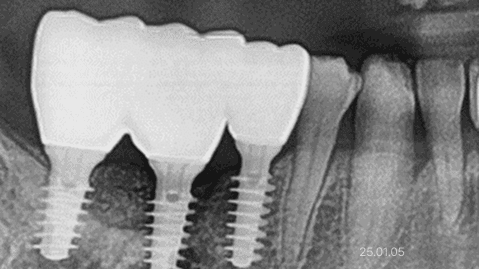

뼈이식 · 전체 임플란트

잇몸뼈 부족 · 타 치과 임플란트 불가판정 · 장기간 틀니 사용

*위 사진은 환자 본인 동의를 얻어 동일 조건에서 촬영 되었습니다. 모든 치료에는 부작용이 발생할 수가 있습니다.